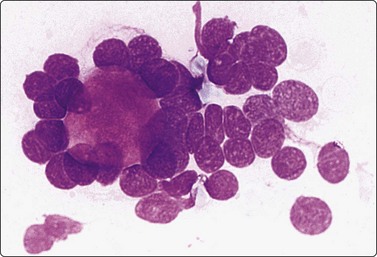

Fig. 4.7 Basaloid squamous cell carcinoma of head and neck

(A) Poorly differentiated cells with squamous features (MGG, HP; (B) Tissue section mimicking adenoid cystic carcinoma (H&E, IP).

Basaloid squamous carcinoma (Fig. 4.7) is a rare distinct variant of squamous cell carcinoma of the head and neck, which is clinically aggressive and has a predilection for the hypopharynx and the tongue. The smear findings are of squamous cell carcinoma without specific features, but a predominance of basal cells may make the distinction from the solid variant of adenoid cystic carcinoma difficult.43